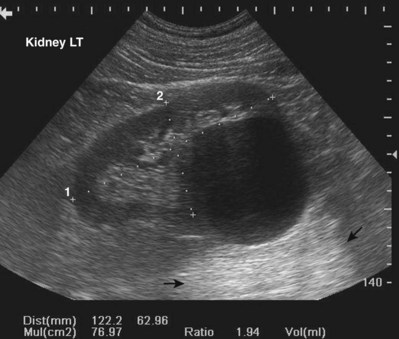

Renal size changes over the lifetime of an individual. Nomograms for pediatric renal size should be consulted. These are based on age, height, and weight of the patient. The average adult kidney measures 10 to 12 cm in length and 4 to 5 cm in width. Measurements of renal volume may be appropriate in cases of severe renal impairment. Renal measurements should be obtained in the midsagittal plane and midtransverse plane. Measurements taken in other than the midsagittal plane and midtransverse may be spuriously low. The thickness of the parenchyma is the average distance between the renal capsule and the central band of echoes. The precise location for making this measurement is somewhat subjective. The midlateral renal parenchyma in the sagittal view is a common choice for obtaining this measurement (Fig. 4–33). Although there is no universal standard, the renal cortical thickness should be greater than 7 mm (Roger et al, 1994), and the renal parenchymal thickness should be greater than 15 mm in adults (Emamian et al, 1993b).

Figure 4–33 The distinction between renal cortical thickness and renal parenchymal thickness is that the renal parenchyma is measured from the central band of echoes to the renal capsule. The renal cortex is measured from the outer margin of the medullary pyramid to the renal capsule.